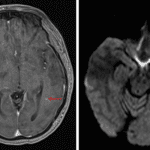

- Large, peripherally-enhancing, centrally necrotic mass bridging the right frontal and parietal lobes measuring 4.5 x 4.2 x 4.5 cm with extensive T2/FLAIR signal hyperintensity in the surrounding white matter

- Restricted diffusion correlating with the enhancing components

- Susceptibility artifact correlating with the area of central necrosis

- Additionally masslike area of restricted diffusion in the posterior left temporal lobe with a corresponding focus of enhancement along its anterior margin

- Mass effect in the right cerebral hemisphere resulting in local sulcal effacement, crowding of the right lateral ventricle, and 9 mm right-to-left midline shift

- Mild dilation of the temporal horn of the right lateral ventricle concerning for entrapment